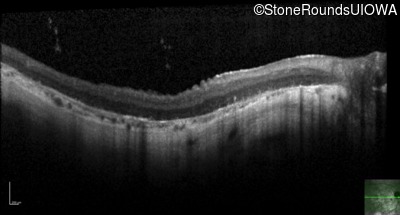

Age at visit: 33 years